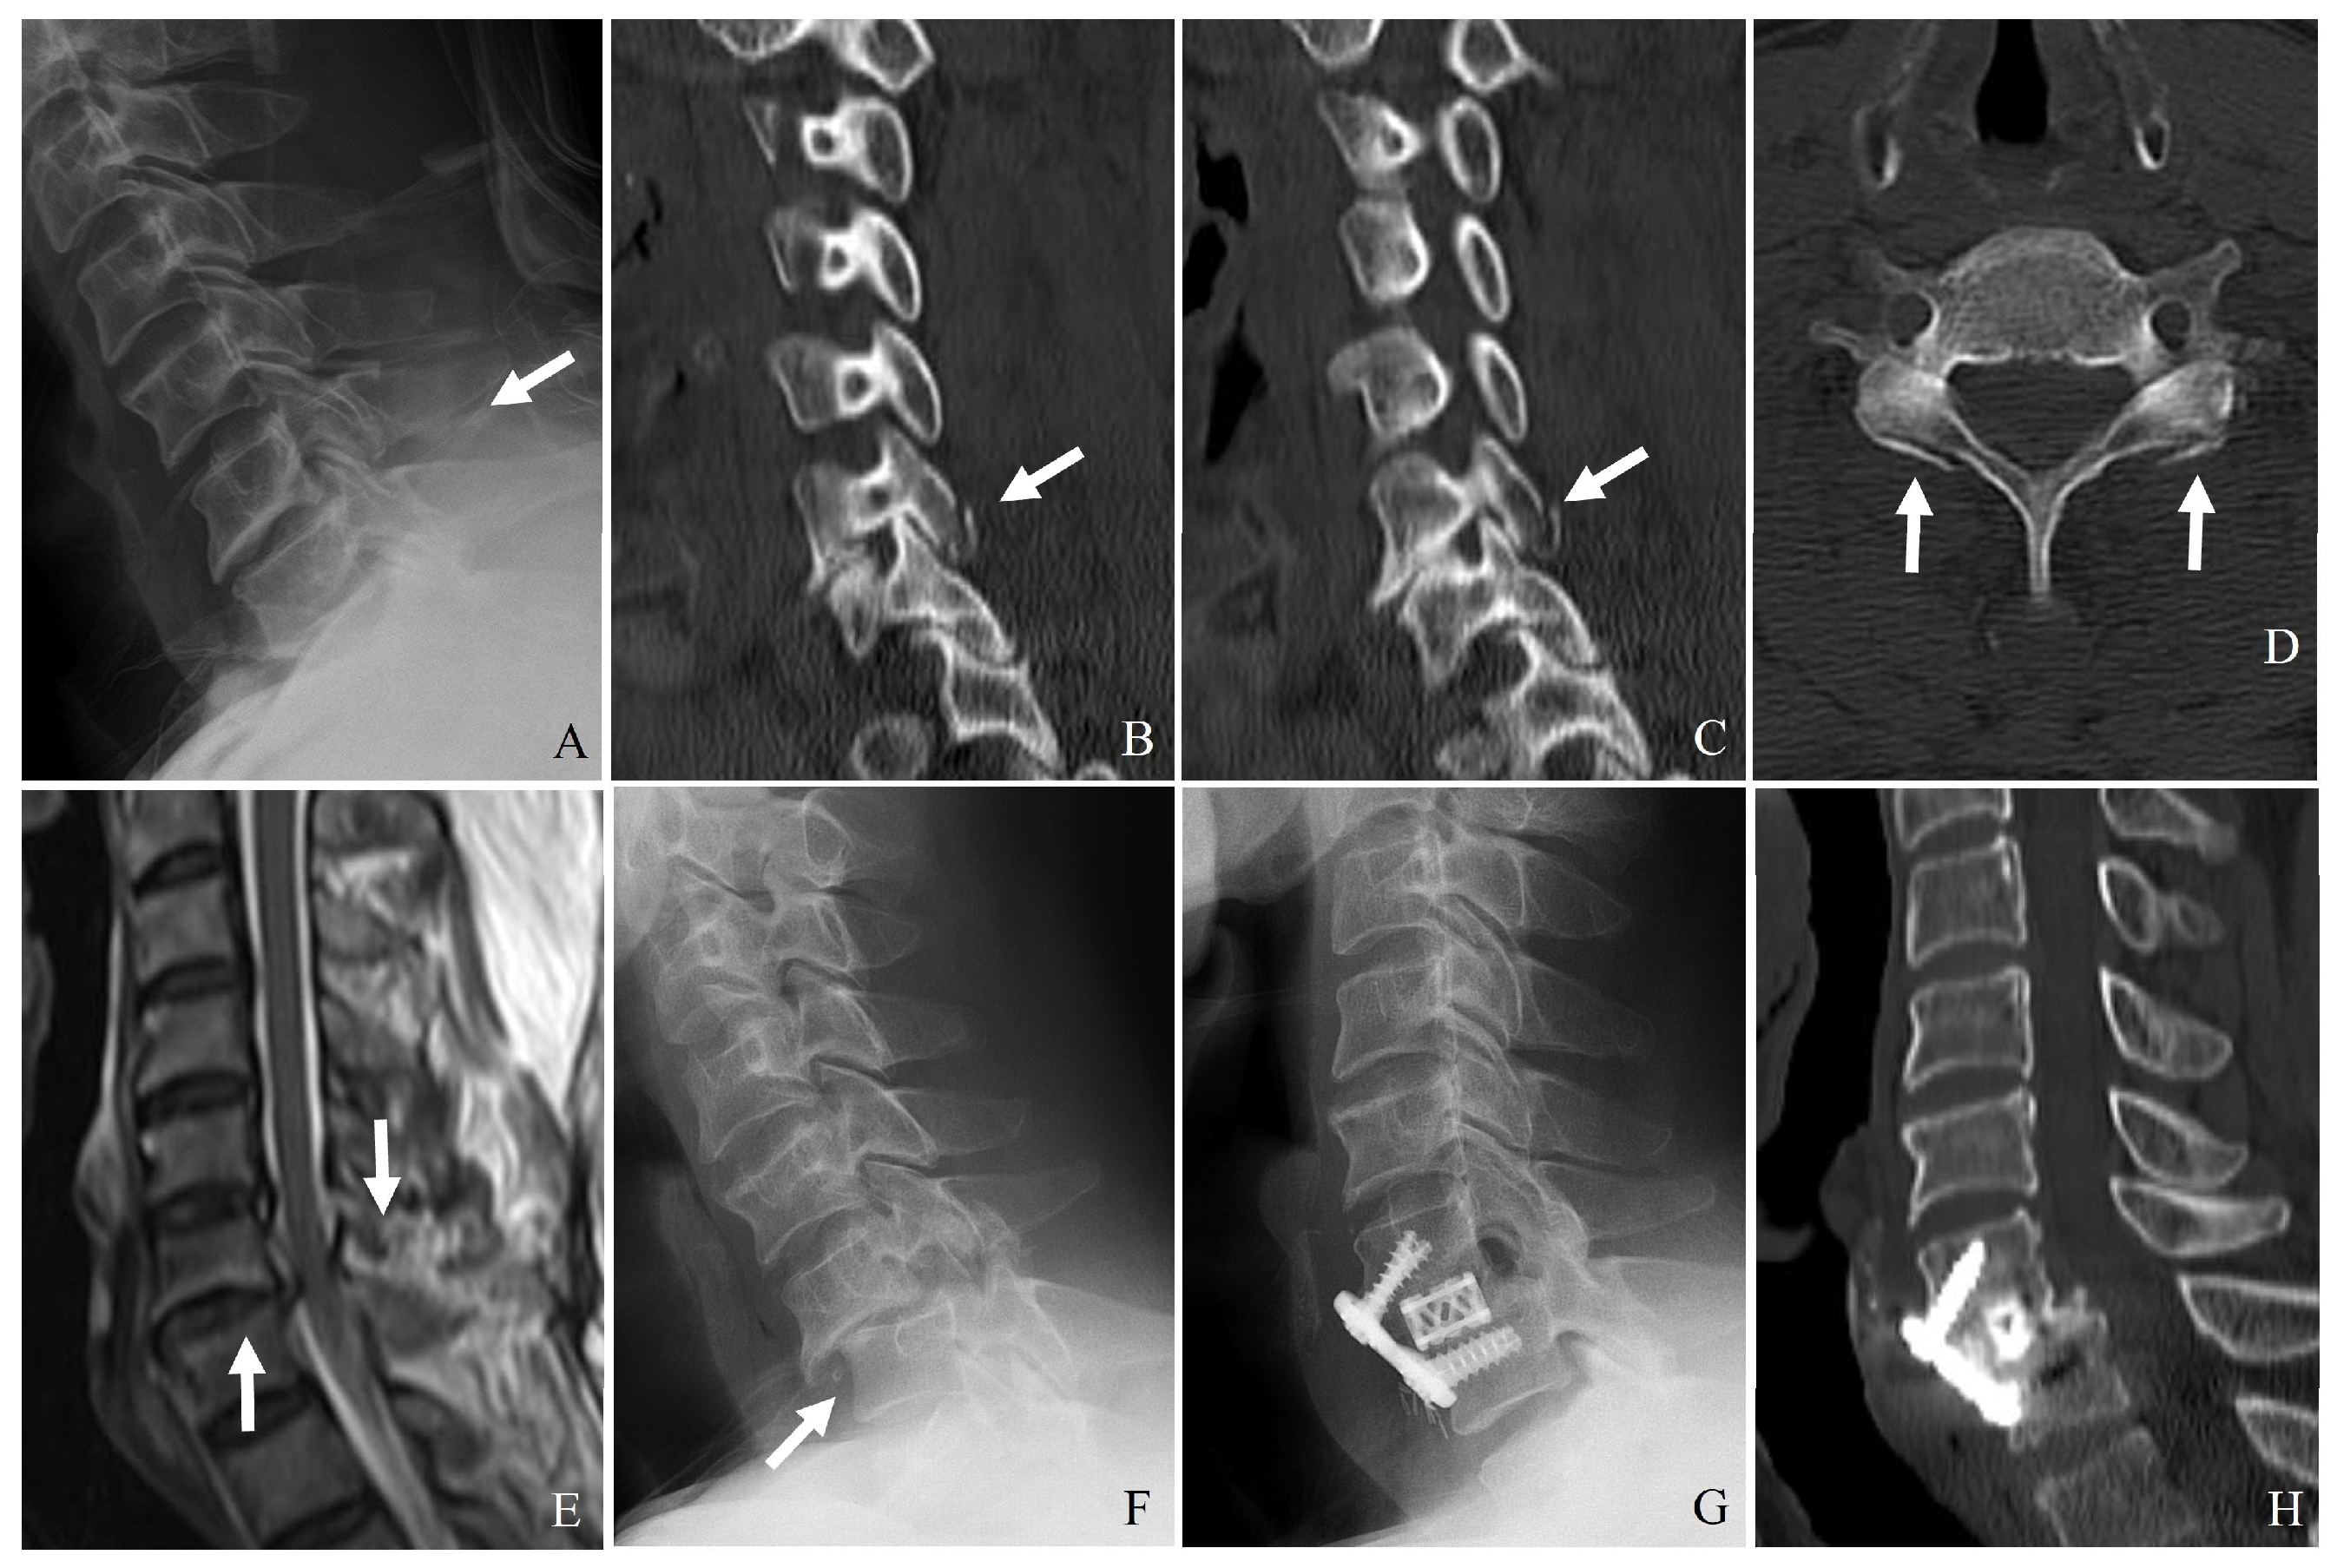

3.1. Plain Radiography

3.2. Computed Tomography (CT)

3.3. Magnetic Resonance Imaging (MRI)